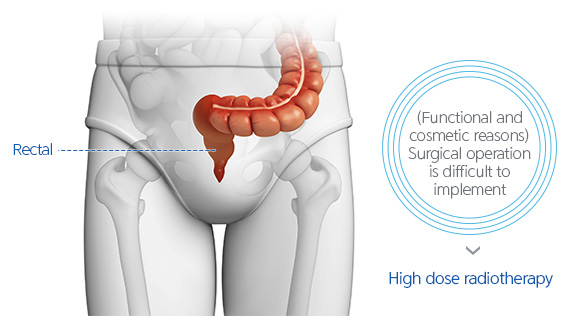

We would like to introduce the details of proton therapy for rectal cancer.

It can be applied before and after surgical operation for recurrent rectal cancers that are difficult to treat with surgical operations.

In the case where radiotherapy has been previously conducted, proton treatment may be the preferred treatment option.

Due to functional and cosmetic reasons, surgical operations may be restrictive. Although high dose radiotherapy is implemented, the level of radiation transferred is limited. Therefore, it is difficult to implement high dose therapy with the X-ray treatments and side effects are common.